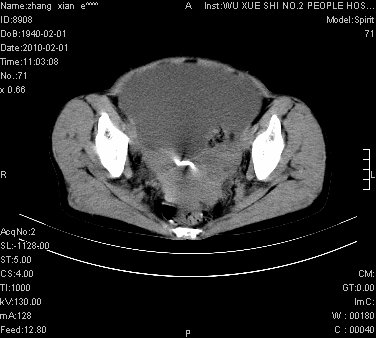

大量腹水,脾脏囊性占位,子宫颈占位,右侧腹股沟淋巴结肿大,建议+c,先查妇科。

腹盆腔大量积液,子宫增大,子宫颈增大外形不规则,内见低密度影,膀胱后壁显示不清,右腹股沟肿大淋巴结,脾脏囊性占位,子宫颈占位,子宫颈癌?建议增强。

腹盆腔大量积液,子宫增大,子宫颈增大外形不规则,内见低密度影,膀胱后壁显示不清,右腹股沟肿大淋巴结,脾脏囊性占位,子宫颈占位,子宫颈癌?建议增强。支持!